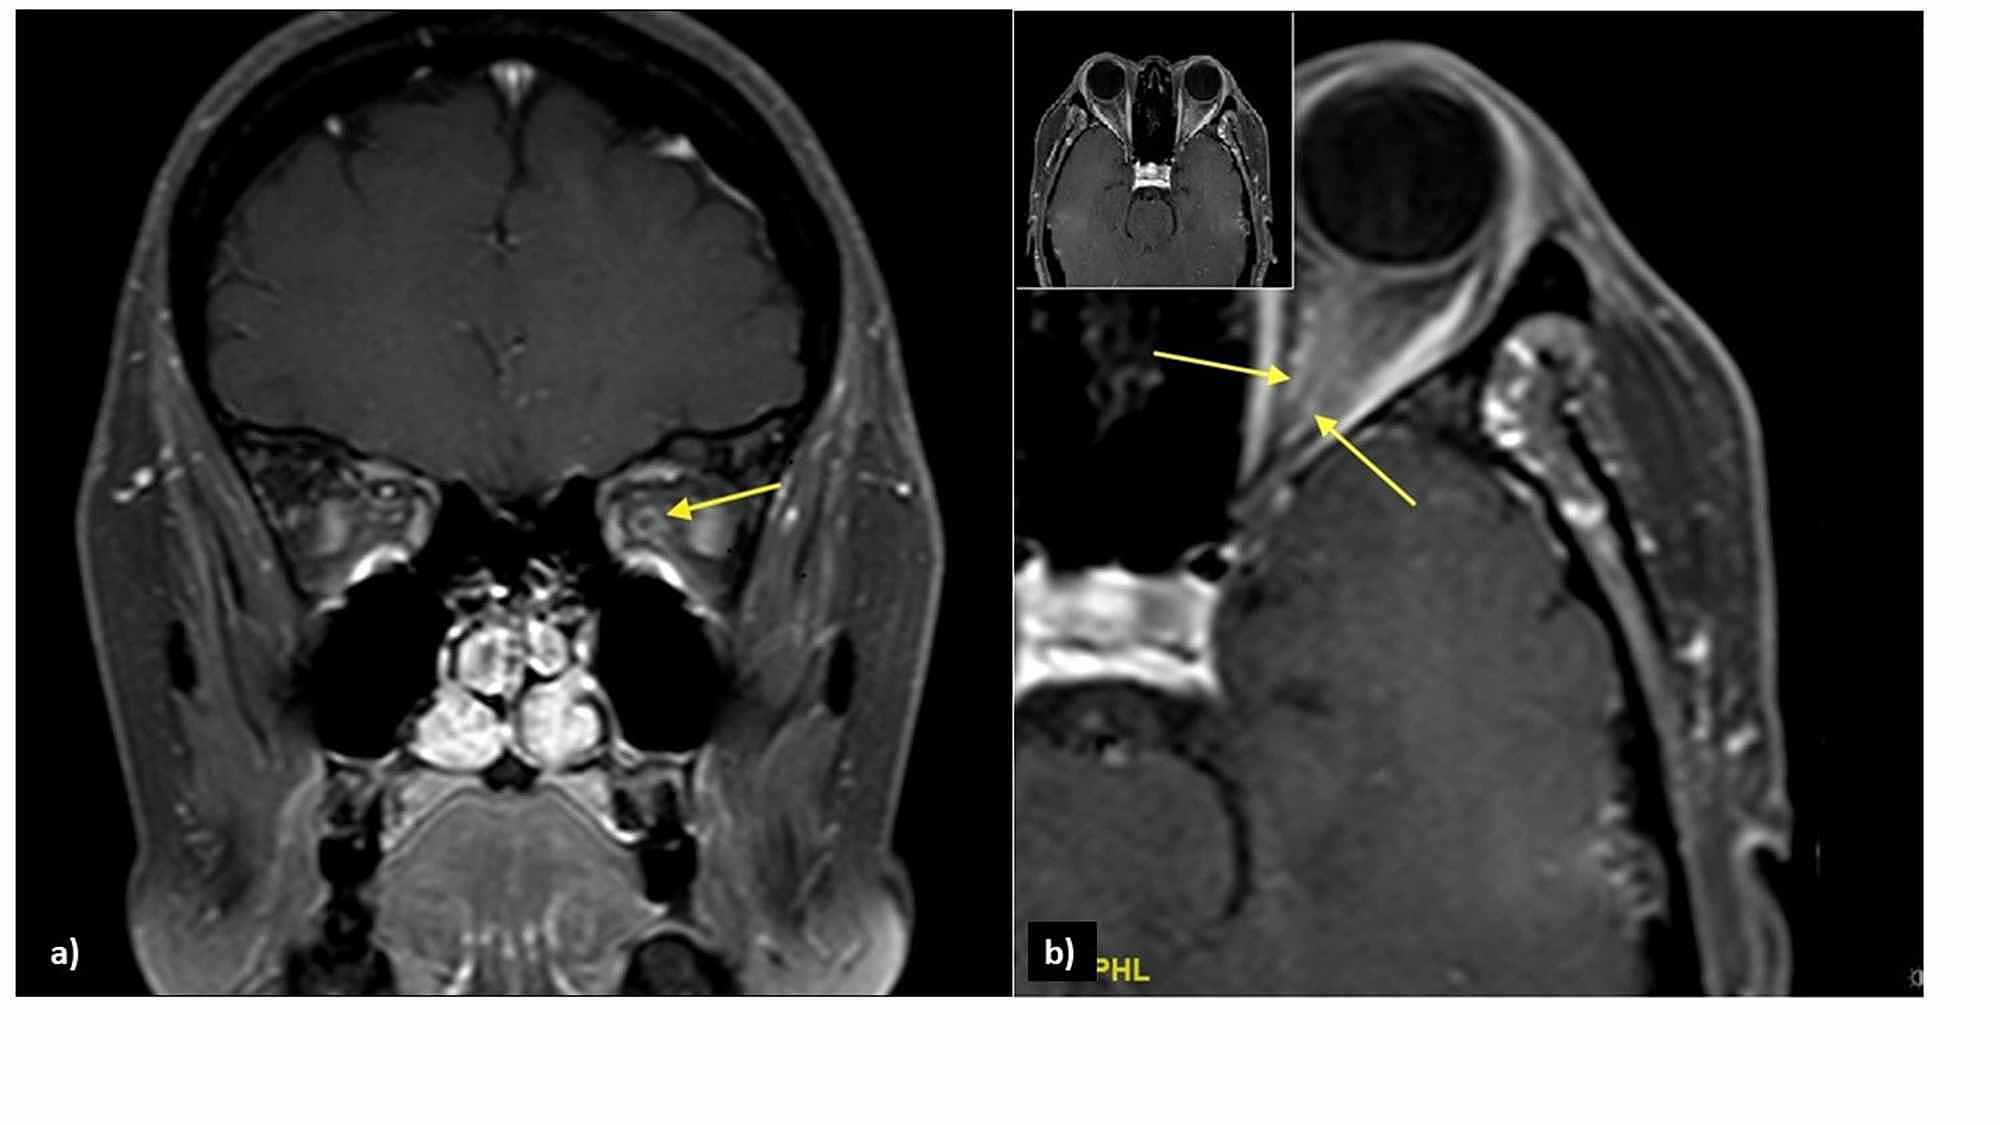

An urgent MRI of orbit revealed an enlarged left intra-orbital nerve (0.45 cm) as compared to the right (0.28 cm). The post-gadolinium contrast MRI showed streakiness and enhancement of periorbital fat surrounding the left optic nerve, with tram-track sign on saggital view, and doughnut sign on coronal sequence, consistent with the left OPN (Figure 2). No abnormalities were detected on MRI of the brain and paranasal sinuses.